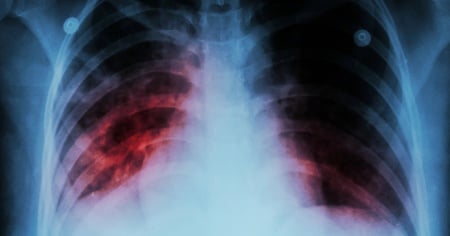

Per l'esattezza, lo scorso anno 543 persone hanno contratto la tubercolosi, 122 in più rispetto al 2024. Questi casi riguardano persone giunte qui da Paesi in cui la malattia è particolarmente diffusa. Per contro, non si rileva un aumento dell’incidenza tra le persone nate nella Confederazione.

Sotto controllo in Svizzera - In Svizzera il rischio di contrarre la tubercolosi è molto basso, e se tuttavia la malattia dovesse presentarsi può essere trattata con successo. In caso di diagnosi precoce, ci sono buone possibilità di guarigione senza conseguenze per la salute. Ad ogni modo, per garantire il pieno recupero, i medicinali prescritti devono essere assunti regolarmente ogni giorno per diversi mesi. Gli uffici cantonali della sanità, i medici e gli specialisti dei servizi cantonali per la tubercolosi tengono sotto controllo questa patologia soggetta a obbligo di dichiarazione.

Diffusa e temuta nei Paesi a basso reddito - Nei Paesi meno privilegiati la tubercolosi resta un grave problema socio-economico, che non deve essere dimenticato. Per effetto della crescita demografica, unità a fattori come instabilità sociale e politica, condizioni igieniche e di vita precarie, malnutrizione e mancanza di accesso ai medicinali e all’assistenza sanitaria, un numero crescente di persone rischia ancora oggi di contrarre la tubercolosi.

Una malattia che è quindi un chiaro esempio delle disuguaglianze globali, poiché colpisce più duramente dove non c’è accesso alle cure.